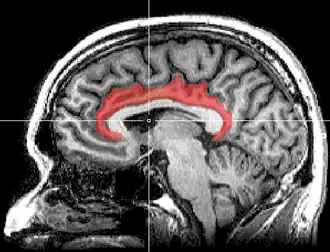

Gyrus cingulaire

Le gyrus cingulaire est un gyrus du lobe limbique du cortex cérébral. Il est situé sur la face médiale des hémisphères, au-dessus du corps calleux. Au-dessus, il est séparé du gyrus frontal supérieur par le sillon cingulaire et du précuneus par le sillon sous-pariétal. En dessous, sa limite est le sillon du corps calleux. Au niveau du splénium du corps calleux, le gyrus cingulaire se rétrécit dans l'isthme qui se poursuit par le gyrus parahippocampique[1].

L'ensemble gyrus cingulaire, gyrus parahippocampique et diverses formations olfactives forment un anneau presque fermé qui s'appelle gyrus fornicatus (en latin, fornicatus signifie « voûté, cintré »).